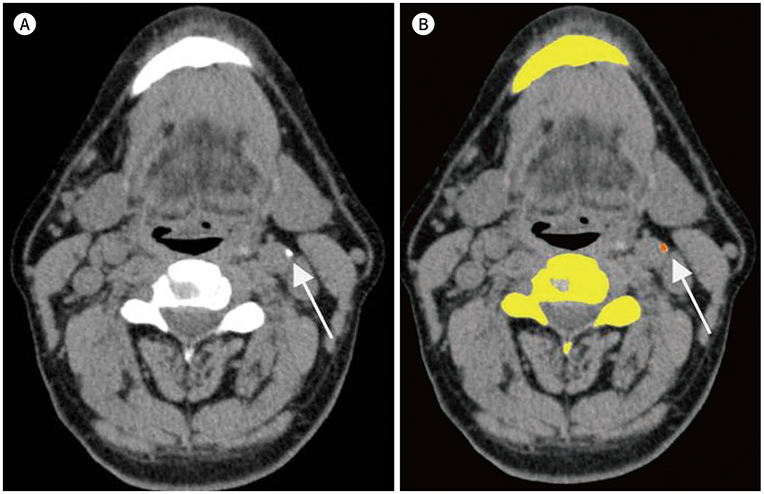

This study involved retrospective evaluation of 60 OSA patients who underwent both upper airway CT and brain MRI. Using polysomnography, several indicators, including apnea index (AI), were used to evaluate the relationship between OSA and silent cerebrovascular lesions. The CarACS was quantified on CT imaging using the modified Agatston method. Silent cerebrovascular lesions were evaluated on brain MRI by grading periventricular hyperintensity (PVH). Various clinical characteristics, including age, were analyzed in each patient.

RESULTS

The number of patients per PVH grade 0, 1, 2, 3, and 4 was 26 (43.3%), 14 (23.3%), 14 (23.3%), 4 (6.7%), and 2 (3.3%), respectively. The mean age, hypertension, smoking status, AI, and CarACS were significantly different among PVH groups (Ps < 0.05). In univariate analysis, the presence of carotid arterial calcification (β = 0.483, p < 0.01), CarACS (β = 0.482, p < 0.01), and age (β = 0.360, p < 0.01) showed a significant association with PVH grade. The mean AI and lowest O₂ saturation had statistically weak associations with PVH grade (β = 0.267, p < 0.01; β = −0.219, p < 0.14, respectively). In multivariate analysis, CarACS was the only factor affecting PVH grade (p < 0.04).

CarACS is associated with the severity of silent cerebrovascular lesions. Therefore, additional analysis of CarACS in OSA patients may provide more information on their cerebrovascular status.